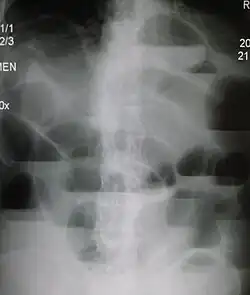

| Upright abdominal X-ray demonstrating a small bowel obstruction. Note multiple air fluid levels. | |

Causes of bowel obstruction include adhesions, hernias, volvulus, endometriosis, inflammatory bowel disease, appendicitis, tumors, diverticulitis, ischemic bowel, tuberculosis and intussusception.[1][2] Small bowel obstructions are most often due to adhesions and hernias while large bowel obstructions are most often due to tumors and volvulus.[1][2] The diagnosis may be made on plain X-rays; however, CT scan is more accurate.[1] Ultrasound or MRI may help in the diagnosis of children or pregnant women.[1]

The main diagnostic tools are blood tests, X-rays of the abdomen, CT scanning, and ultrasound. If a mass is identified, biopsy may determine the nature of the mass.

Radiological signs of bowel obstruction include bowel distension (small bowel loops dilated >3 cm) and the presence of multiple (more than 2) air-fluid levels on supine and erect abdominal radiographs.[16] Ultrasounds may be as useful as CT scanning to make the diagnosis.[17]

Contrast enema or small bowel series or CT scan can be used to define the level of obstruction, whether the obstruction is partial or complete, and to help define the cause of the obstruction. The appearance of water-soluble contrast in the cecum on an abdominal radiograph within 24 hours of it being given by mouth predicts resolution of an adhesive small bowel obstruction with sensitivity of 97% and specificity of 96%.[18]